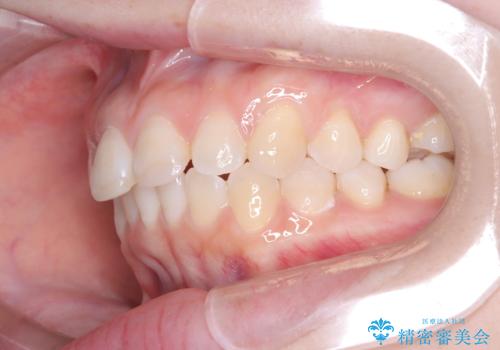

- 前歯のデコボコ(叢生)を気にされてご来院されました。精密な検査の結果、歯が並ぶスペースが不足していることが判明。患者様のご希望から、透明で目立ちにくいインビザライン(マウスピース矯正)による治療計画を立案しました。抜歯を避け、奥歯全体を奥へ動かす遠心移動という方法でスペースを確保し、前歯の叢生を解消することを目指します。

今回の矯正治療では、透明なマウスピース型の装置インビザラインを使用しました。この装置は取り外し可能で、日常生活で目立ちません。治療は、緻密に計算された計画に基づき、段階的に作製されたマウスピースを交換していくことで、奥歯から順に全体を後方へ移動させる遠心移動を実施。これにより、前歯を並べるための十分なスペースが確保され、デコボコが解消されました。抜歯することなく、機能的にも審美的にも整った美しい歯並びを獲得していただけました。